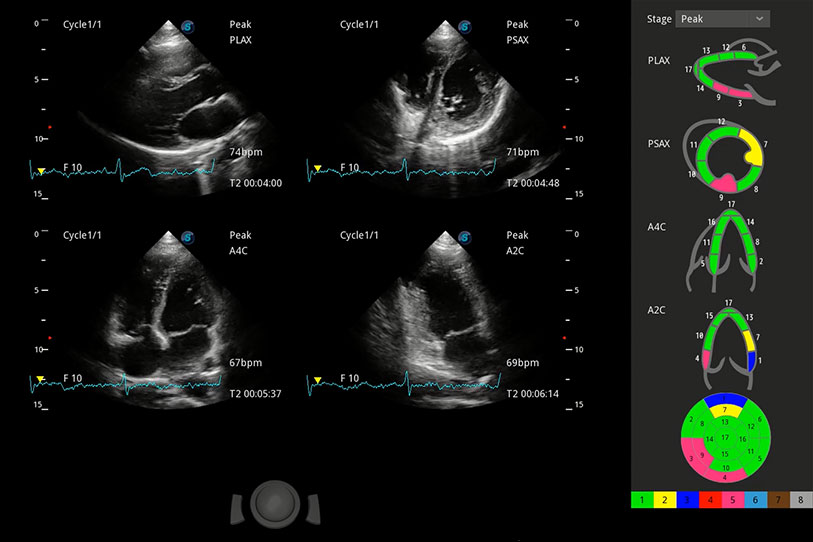

具備多種協(xié)議可選,同時(shí)支持17階段劃分法和專(zhuān)業(yè)的SE報(bào)告。